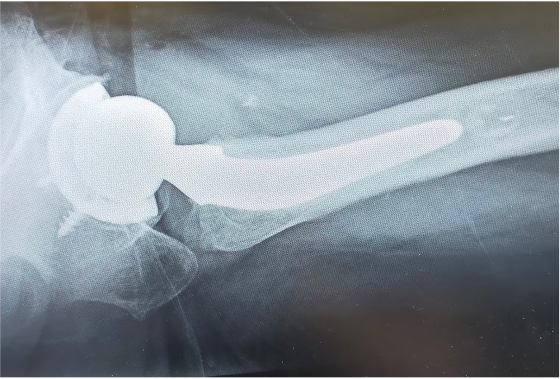

〈手術後のレントゲン〉(側面)

当院にて人工股関節全置換術(THA)を施行。

アプローチはAMIS(前方最小侵襲手術)で行い、翌日から歩行器での歩行訓練を開始。

術後2日目には杖なしでの歩行、術後4日目で階段昇降が可能となり、術後1週間程で退院となりました。